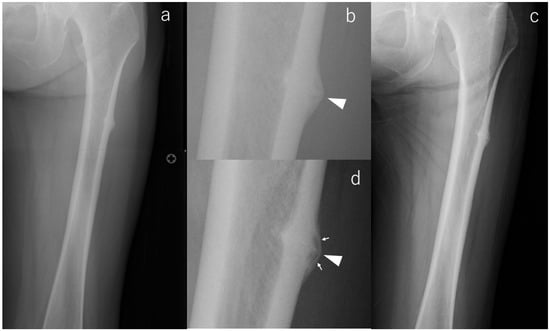

Radiographic Evolution of Contralateral Asymptomatic Incomplete Atypical Femoral Fractures in Autoimmune Disease Patients

Background/Objectives: Atypical femoral fracture (AFF) represents a diagnostic and therapeutic challenge, particularly in autoimmune disease patients receiving long-term bisphosphonate (BP) and glucocorticoid (GC) therapy. Although bilateral AFF is common, the radiographic evolution of asymptomatic incomplete lesions identified at the time of a complete fracture remains insufficiently defined. This study aimed to characterize the natural history and imaging biomarkers associated with progression in this biologically homogeneous high-risk population. Methods: Ten female autoimmune disease patients with complete AFF and asymptomatic incomplete contralateral lesions were retrospectively evaluated over a mean 59 months. Serial radiographs were assessed for cortical beaking, periosteal flaring, and transverse radiolucent lines. All patients discontinued BP therapy postoperatively; teriparatide was administered when tolerated. Results: Six lesions regressed, three remained stable, and one progressed—this progressing case being the only limb with a transverse radiolucent line at baseline. No patient developed symptoms or sustained a complete fracture on the contralateral side. Radiographic remodeling occurred independently of symptoms. BP discontinuation and, when tolerated, teriparatide appeared to contribute to lesion stabilization, although statistical significance was not achieved. Conclusions: In autoimmune patients with severe long-term BP and GC exposure, most asymptomatic incomplete AFF identified at the time of contralateral complete fracture remains stable or improves under conservative management. A transverse radiolucent line is the most decisive imaging biomarker predictive of progression and warrants intensified surveillance or consideration of prophylactic fixation. Larger cohorts are needed to refine risk stratification algorithms and optimize diagnostic and management strategies. Full article

Figure 1